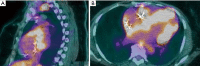

In the era of Precision Medicine, diagnostic imaging plays a key role in initial diagnosis and treatment response assessment in thoracic manifestation of various rheumatic disorders; resulting in increased dependency on imaging for treatment planning. Chest radiographs serve as a good initial screening tool for assessment of emergent and urgent thoracic conditions, e.g., pneumothorax, pulmonary edema, consolidation and pleural effusions. Cross-sectional imaging techniques, e.g., computed tomography (CT) and positron emission tomography-computed tomography (PET-CT) are most commonly utilized to evaluate more detailed pulmonary and mediastinal manifestations of rheumatic conditions. Magnetic resonance imaging (MRI) and ultrasound are most commonly used in cardiovascular, neural and musculoskeletal structures. This review article aims to highly key common thoracic imaging findings of rheumatic disorders, highlighting imaging test of choice for the particular disorder.